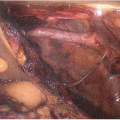

Leave both adrenal glands attached to the kidneys until after graft reperfusion when they are excised (FIG 1). Ligate and divide the left and right adrenal vein in close proximity to each adrenal gland. Carefully ligate and divide the tissues connecting the inferomedial aspect of each adrenal gland to the hilar structures. The adrenal glands can now advantageously be used as handles to avoid grasping the kidneys themselves. Tie each end of a long 4-0 silk to the adrenal glands’ upper pole, creating effectively a bucket handle-like structure that can be used for atraumatic lifting of the kidneys as they are being placed on pump, for manipulation while on pump, and at the time of the implantation.